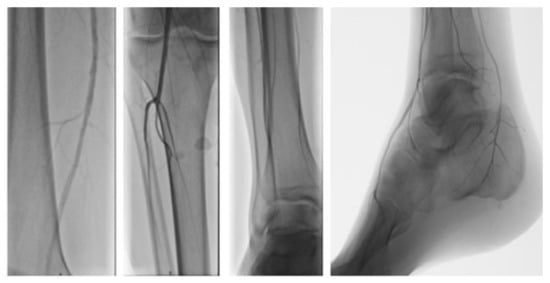

2. Case Presentation